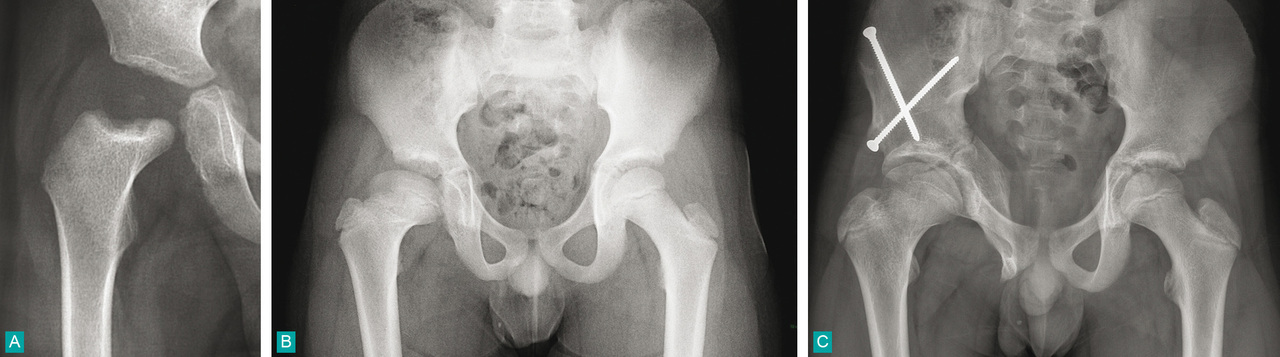

A. Radiographie de la hanche droite d'un garçon de 3 ans avec nécrose de la tête fémorale, élargissement et ostéolyse métaphysaire.

B. Évolution à 9 ans avec coxa magna et défaut de couverture de la tête fémorale.